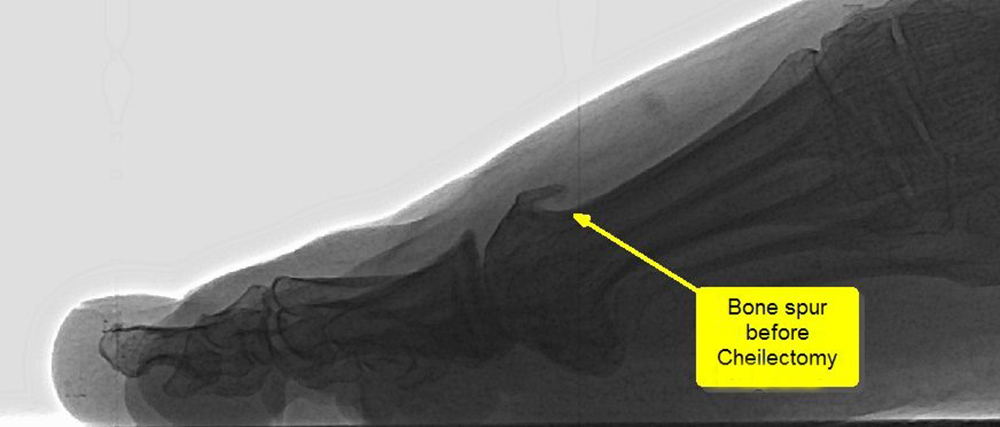

A cheilectomy is a surgical procedure to remove a bony lump (made up of bone spurs) on the top of the big toe's main joint.

This operation treats degenerative arthritis, which occurs when bony spurs press painfully on the shoe. Bone spurs form around the joint as part of the degenerative process. They may restrict the joint's motion, especially the toe's ability to bend upward when the foot moves forward.

The surgeon cuts the top of the big toe joint over the spurs and removes them so they will not bump together when the toe extends. This allows the toe to bend better and reduces the amount of pain when walking. Sometimes, the surgeon will remove a little extra bone to ensure that nothing rubs when the toe bends upward. The surgeon then flushes out the joint, stitches it up the incision, and applies a dressing. The cheilectomy takes about 20-30 minutes and is most often performed as an outpatient procedure under either local or general anesthesia. Most people with a cheilectomy can go home the same day.